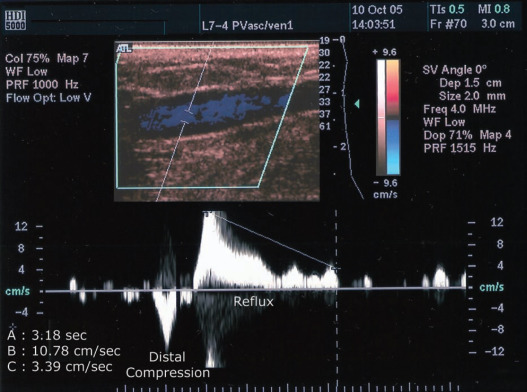

<p>what is being shown in this image?</p>

what is being shown in this image?

venous reflux